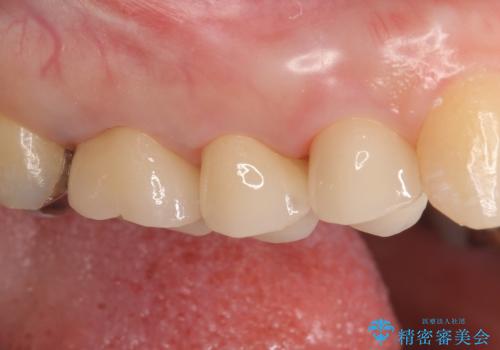

今回用いたオールセラミッククラウンはジルコニアフレームという白い素材の上にセラミックを盛っているため、審美性が非常に高いのが特徴です。

また、ジルコニアは人工ダイヤモンドの材料にも使われているほど高い強度を持っており、そのためオールセラミッククラウンは審美性だけでなく、奥歯やブリッジの補綴も可能とするクラウンです。